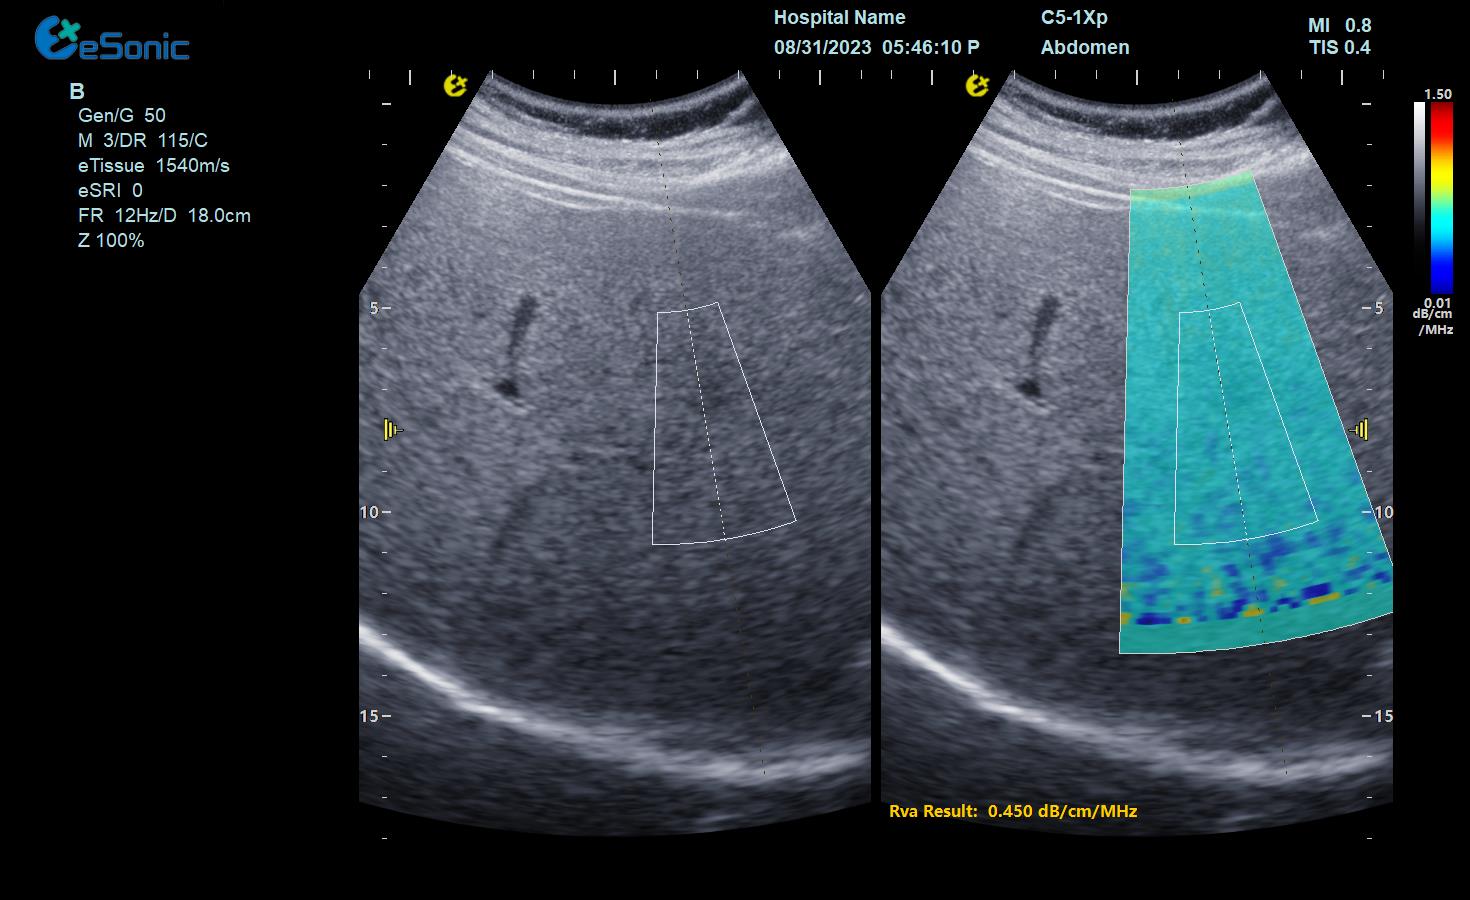

肝脏RVA